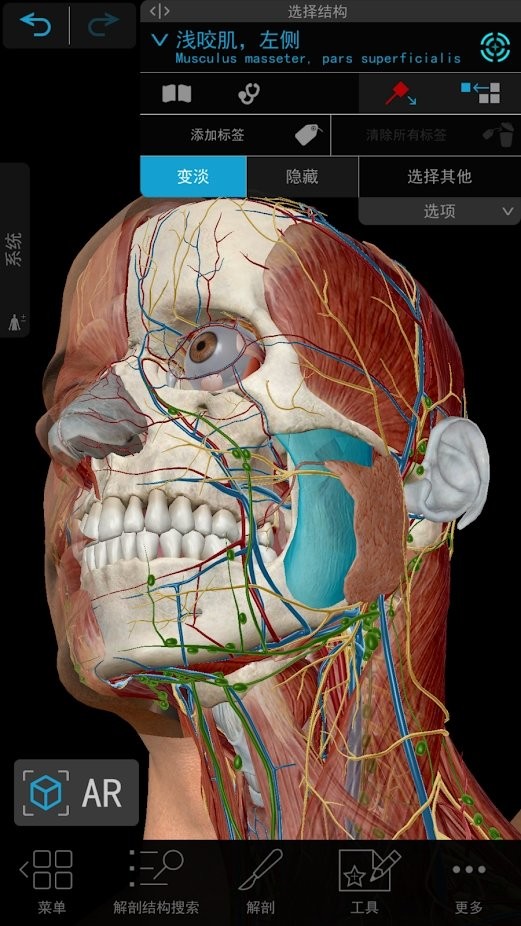

#2021人体解剖图谱 截图